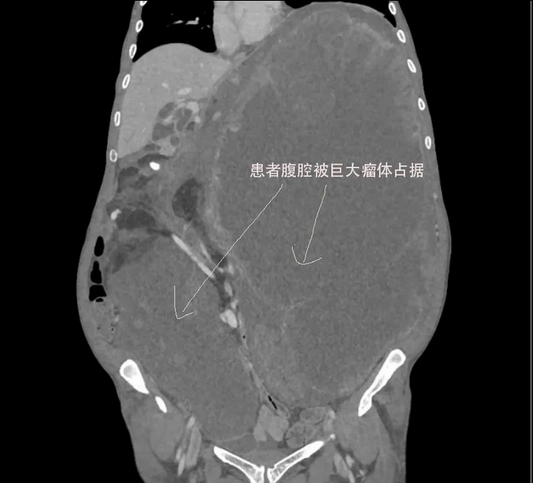

🏥Life Within a 17.5kg Tumor: A Deep Dive into Surgical Decision Logic

This case provides an in-depth analysis of the clinical decision-making path for a 17.5kg giant recurrent leiomyosarcoma by a Beijing expert team. By distinguishing "physical compression" from "anatomical infiltration" through...